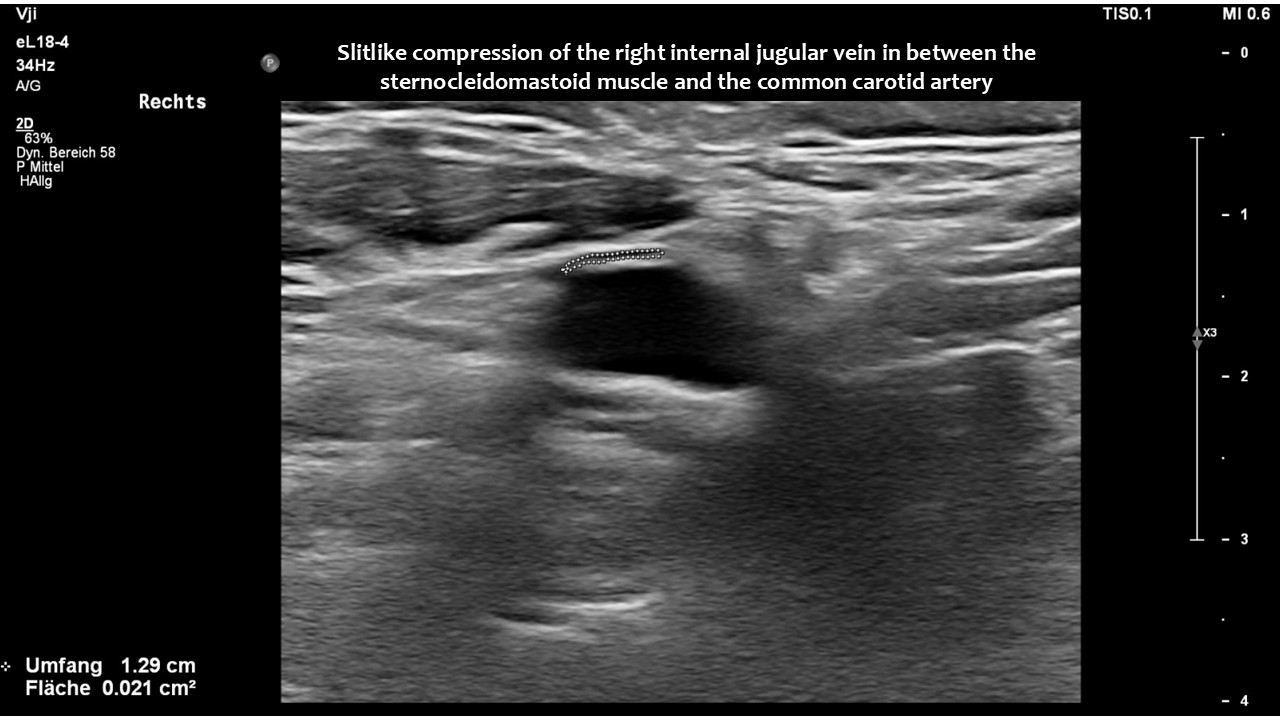

However, in this patient, both jugular veins were compressed. The middle portion of the internal jugular vein was pushed ventrally by the increased cervical lordosis on both sides, becoming squeezed between the carotid artery and the sternocleidomastoid muscle.

Consequently, blood had difficulty leaving the skull, resulting in continuously increased pressure and severe headaches, as well as other neurological dysfunction. The left side was more affected due to the double compression. This was clearly demonstrated by four-dimensional volume flow measurements in both jugular veins.

Only a four-dimensional volume flow measurement of the jugular veins can determine the cause of the daily headaches. The overall reduction in venous outflow from the brain in both jugular veins, totalling 258 mL/min, is significantly lower than the normal average volume of 719 mL/min. Consequently, the patient can eliminate only 36% of the required flow volume, while additional volume is forced into the skull from the left renal vein via the tronc réno-rachidien and from the left common iliac vein via the left ascending lumbar vein. This results in a chronic increase in intracranial pressure, as demonstrated by the elevated cerebrospinal fluid pressure obtained through a lumbar puncture. When the left jugular vein is also completely compressed due to increasing cervical lordosis when upright, the headaches become unbearable, accompanied by additional neurological symptoms as described by the patient.

Without this sophisticated technique, it would be unclear how severe the pressurization of the skull was and that, despite compression of both jugular veins, the right one was the main escape route from the skull.